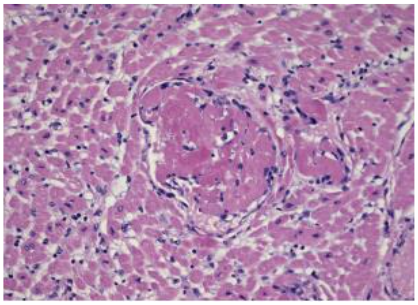

On the contrary, a child who had acute myocarditis caused by a cardiotropic virus (Coxsackie) has a completely different picture, in which eosinophils, lymphocytes, and plasma cells dominate, and the muscles are edematous (Fig. 2).⁸,¹¹

Fig. 2.

Acute myocarditis – light microscopy (Dallas criteria); shows massive interstitial infiltrates of lymphocytes, plasma cells, and eosinophils.

Muscle fibers are partially edematous and hypereosinophilic.

*HE, enlargement 100x.*¹¹